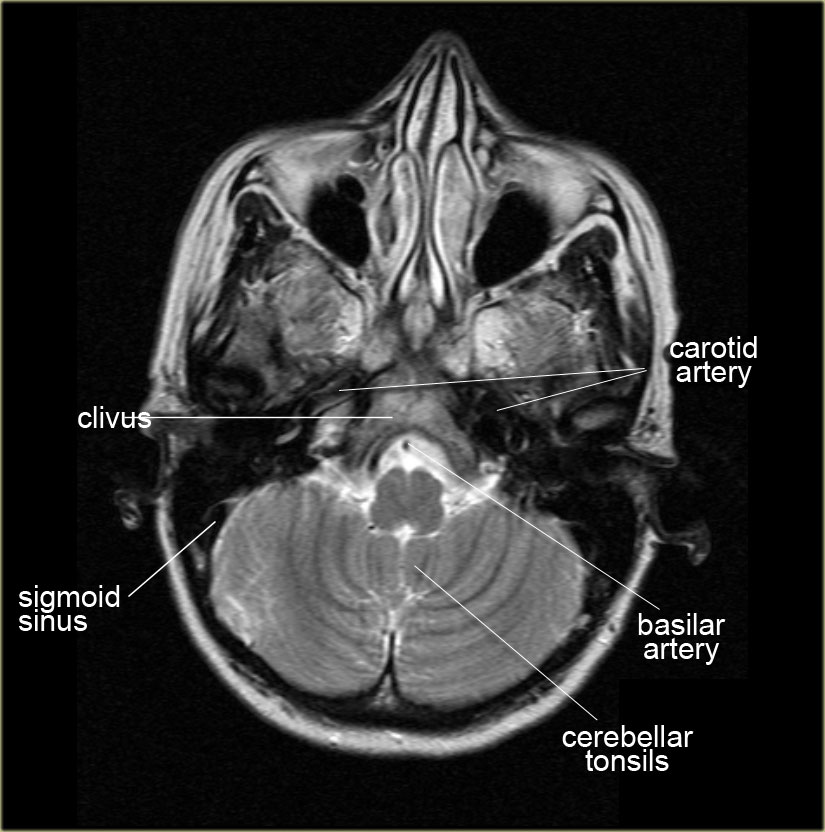

Ct skull base anatomy. You can however go directly to any section using the links below. B axial ct image with color coded overlay shows the skull base bones. The skull base can be evaluated by computed tomography ct which will demonstrate the bony structures of the skull base with its foramina and fissures for vessels and cranial nerves the temporal bone and sinonasal cavities.

2 superior orbital fissure. Ct is superior to mri for subtle cortical bone changes but marrow processes are best characterized with non gadolinium gd contrast enhanced t1 mri. For lesions that are completely intraosseous the mass may only be appreciated on mri figure 1.

Ct anatomy of skull base. Blue central skull base csb purple posterior skull base teal anterior skull base asb. Foramina of the skull base and the structures that pass through them.

Cranial foramina for further details. A axial three dimensional reconstructed ct image with color coded overlay shows the skull base sections. Ct anatomy of skull base.

The base of the skull is perforated by numerous foramina which allow vessels and nerves to pass through the base of the skull allowing the intracranial cavity to communicate with the rest of the body see main article. Skull ct anatomy the sagittal suture is the line where the right and left parietal bone are in contact. A noncontrast sinus or skull base ct which covers the mastoids temporal bone and entire skull base is recommended and intravenous contrast is not usually necessary as the mri will provide soft tissue detail.

Ct is more sensitive in detecting fibro osseous skull base lesions calcification and sclerosis. The module interface is meant to mimic a radiology workstation with adjacent image scrolling via arrow keys and or mouse wheel button. Navigating the skull base identify the petro occipital fissure to navigate the major structures of the skull base.